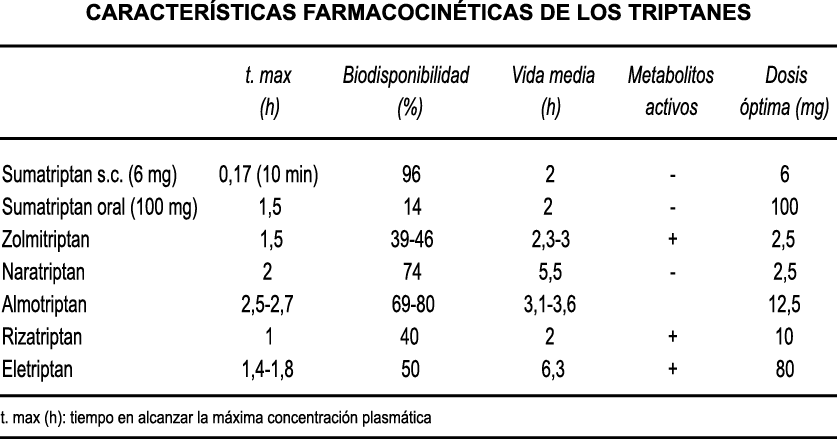

Posteriormente diversos estudios demostraron que la infusión de 5-HT podría abortar tanto la cefalea inducida por reserpina(55) como la espontánea(56). En respuesta a estos estudios, el sistema del receptor 5-HT ganó mucha atención, lo que culminó con el descubrimiento de los triptanos, la serotonina y los agonistas del receptor 5-HT1B/1D(57). Todos exceptuando el 5-HT3 (canal iónico controlado por ligando) son receptores acoplados a proteína G. Si bien los triptanos se clasifican como agonistas de los receptores 5-HT1B/1D, la mayoría también activa en menor medida los receptores 5-HT1A, 5-HT1E o 5-HT1F(58). Originalmente, los triptanos se desarrollaron para actuar sobre la vasculatura craneal, una idea apoyada por sus claras acciones vasoconstrictoras(59) (Figura 25) y la expresión preferencial del receptor 5-HT1B en los vasos craneales más que en los periféricos(60).

A pesar de la clara farmacología de los triptanos en el tratamiento de la migraña, su uso es limitado en pacientes con factores de riesgo cardíaco(61), lo que obliga a dirigirse a receptores que carecen de acción vasoconstrictora. Una de esas dianas es el receptor 5-HT1F, que es activado hasta cierto punto por algunos triptanos, como el naratriptán y no por otros, como el rizatriptán(62). (Tabla 2)